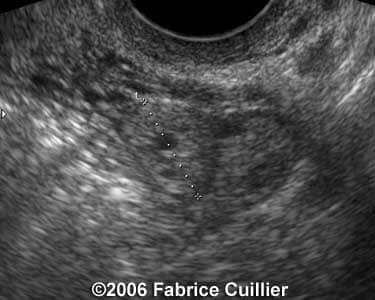

Case 3

case3a

case3b